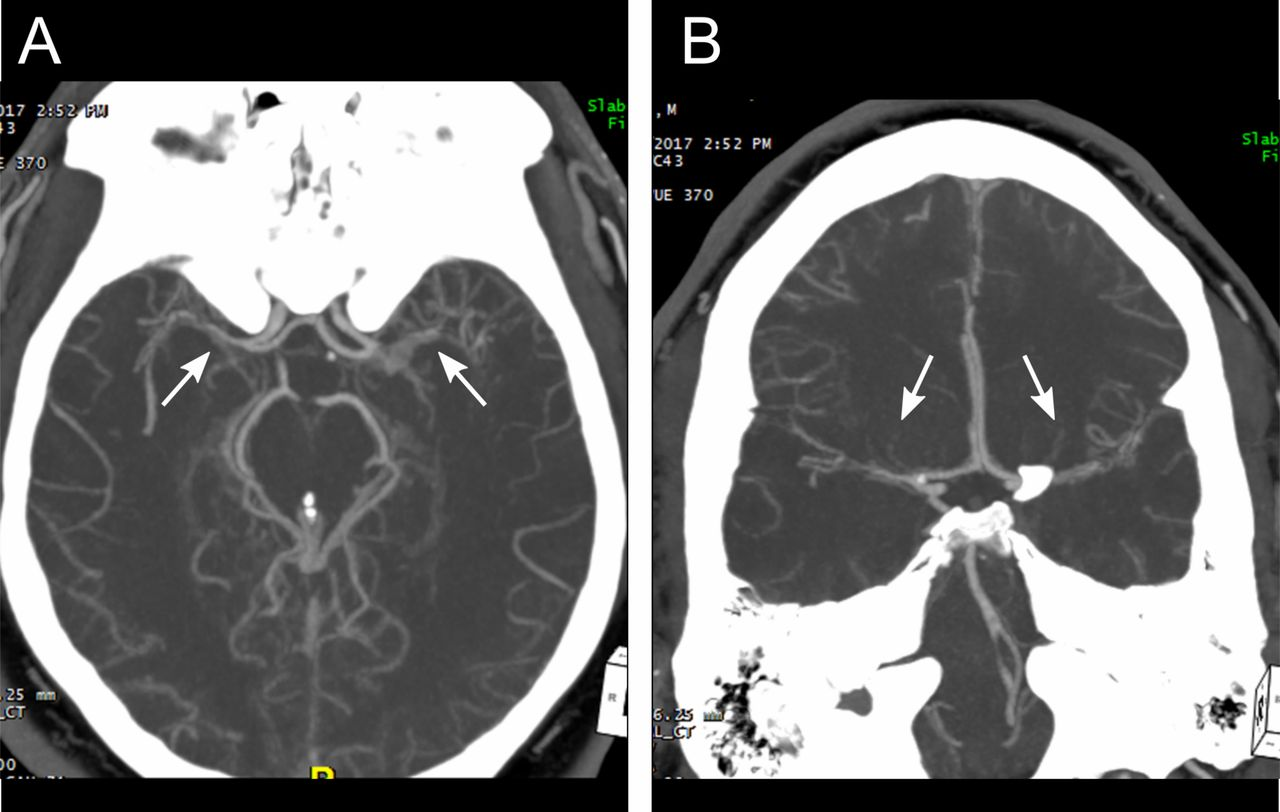

47 35 歲健康女性,早上起床時,突然發生失語症,右側肢體無力,經腦部核磁共振掃描檢查結果如下 圖,其最可能的診斷為何?

病因學: 最早的毛毛樣腦血管病(Moyamoya disease)是內頸動脈血管有多出來的側支循環、X光片很像毛玻璃,像霧(日文為Moya Moya)稱之。一種慢性進行性腦血管閉塞疾病,由於顱內大血管閉塞,導致小血管代償性雜亂無章地瘋長,異常毛細血管亂麻成一團,而形成煙霧狀,所以也稱之為“煙霧病”。